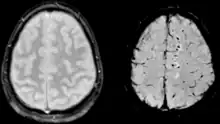

Comparison of diffuse axonal injury imaged with conventional GRE (left) and SWI (right) at 1.5 T

Comparison of hemorrhage imaged with conventional GRE (left) and SWI (right) at 1.5 T

The detection of micro-hemorrhages, shearing, and diffuse axonal injury (DAI) in trauma patients is often difficult as the injuries tend to be relatively small in size and can be easily missed by low resolution scans. SWI is usually run at relatively high resolution (1 mm3) and is extremely sensitive to bleeding in the gray matter/white matter boundaries making it is possible to see very small lesions increasing the ability to detect more subtle injuries.